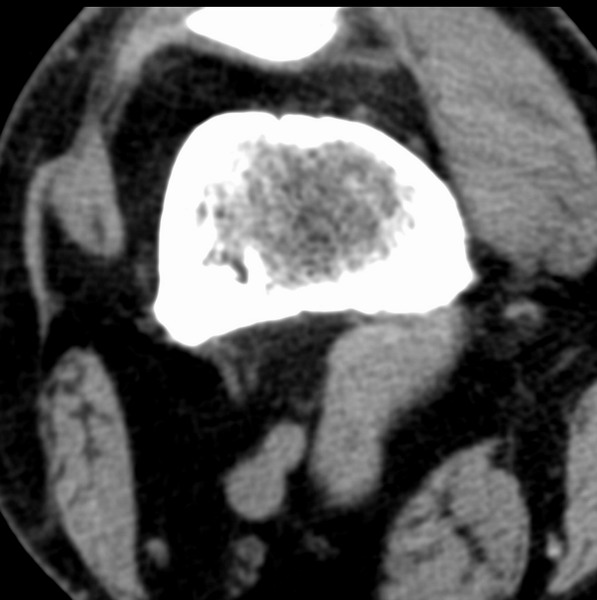

标题: CT21959:骨肿瘤请会诊。

右侧膝关节疼痛一月

男、48

股骨下段、胫骨上段。

1、股骨干骺端病变考虑干骺端纤维性皮质缺损愈后(非骨化性纤维瘤)改变,胫骨近端内生骨瘤(或干骺端纤维性皮质缺损愈后改变);

2、骨关节炎,骨质增生,股骨外侧髁退变性囊肿(关节面软骨下囊肿);

3、髌骨前缘裂纹骨折?